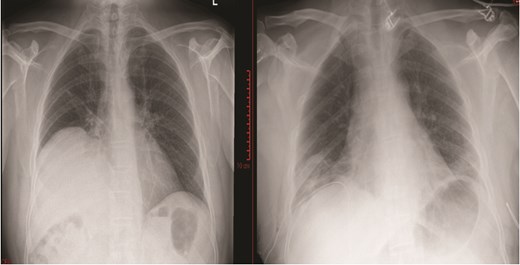

A 53-year-old man presented with a 6-month history of shortness of breath and cough. His chest X-ray showed elevation of the right hemidiaphragm (Fig. 1) and the computed tomography (CT) scan noted no external compression or invasion to the right phrenic nerve alongside a significant loss of volume of the right lower and middle lobes due to compression from the liver and elevated diaphragm. An ultrasound sniff test demonstrated paradoxical movement of the right hemidiaphragm: while the left hemidiaphragm descended during inspiration, the right remained static—consistent with right phrenic nerve palsy.

Chest X-ray prior to diaphragmatic plication (left); chest X-ray post diaphragmatic plication (right).

He underwent a RATS plication of the right hemidiaphragm after a year of watchful waiting to assess for spontaneous recovery. The diaphragm was plicated with multiple horizontal mattress 2/0 ethibond sutures reinforced with pledgets and secure with Coreknot device to plicate the diaphragm as it was quite tense and placing the knots with the robotic instruments was difficult. CO2 insufflation was performed up to 8 mmHg to assist in the procedure. Then multiple horizontal mattress 0 ethibond sutures reinforced with pledgets were used to provide additional support to the plication repair and were tied using the robotic instruments. Postoperative chest x-ray showed the right hemidiaphragm in an improved position (Fig. 1).